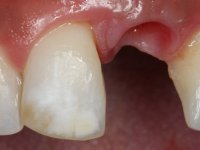

A paciente de sexo feminino de 28 anos de idade perdeu por traumatismo o incisivo central superior esquerdo. Preocupada com o seu sorriso, a paciente apareceu no consultório querendo alinhar os dentes antero-superiores para obter uma aparência mais natural. Sendo fumadora a paciente não apresentava problemas médicos dignos de registo.

A paciente apresenta um desvio da linha média superior de 6 mm para a esquerda. Resultado da ausência do incisivo central superior esquerdo, os dentes adjacentes inclinaram mesialmente para esta zona, limitando o espaço disponível para a reabilitação prostodontica. Existe uma significativa desarmonia dentária negativa no arco maxilar como resultado da ausência do 21, ausência do primeiro pre-molar com um espaço residual, significativa redução coronária do segundo pre-molar direito, migração dos dentes posteriores para os espaços não preenchidos e uma mesialização molar superior esquerda e direita com uma relação molar em Classe II. Ambos os caninos esquerdo e direito mostram uma relação Classe II na posição de inter-cuspidação máxima. A paciente apresenta uma linha de sorriso média, um biótipo gengival médio grosso, apresenta uma correcta higiene oral sem doença periodontal. Não apresenta hábitos para –funcionais. O exame radiográfico mostra uma significativa inclinação dos eixos dos dentes 11 e 22 com espaço entre a porção apical das raízes. A análise cefalométrica foi feita com o intuito de explorar a hipótese de conseguir arranjar espaço para a colocação de um implante e de uma coroa no local do dente 21. Finalmente a morfologia do osso residual presente na região anterior da maxila foi avaliado com uma TAC, revelando uma perda das dimensões da parede óssea vestibular.